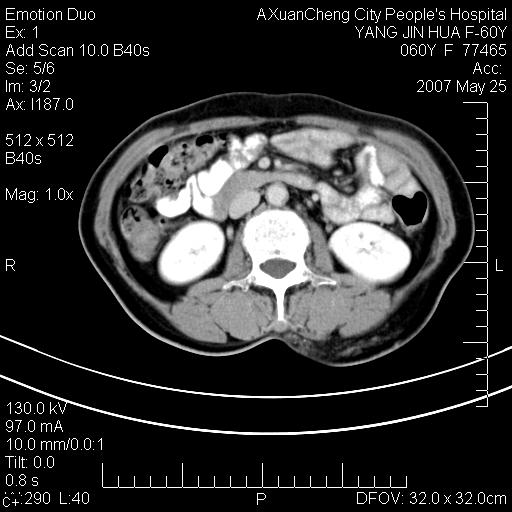

发现左侧腰背部包块40余年,逐渐长大,质软,局部表面可见扩张的血管影

左背部皮下良性肿瘤,密度不均,边界不清,内有脂肪、钙化,增强扫描无明显强化,血管平滑肌脂肪瘤?进一步诊断有困难,建议穿刺活检。

左侧背部皮下混杂密度肿块,结构较疏松,边缘欠光整,内有多发斑点状钙化,考虑:皮下血管瘤。

左背部皮下良性肿瘤,密度不均,边界不清,内有脂肪、钙化,增强扫描无明显强化,血管平滑肌脂肪瘤?进一步诊断有困难,建议穿刺活检。还有,我想还是问一下病史,患者有外伤史吗?能否完全排除外伤后机化的....

血管平滑肌脂肪瘤,支持!另应详细了解病史,待除外骨化性肌炎。

还是考虑皮下血管瘤,强化不明显可能跟大量血栓形成有关,好多战友考虑血管平滑肌脂肪瘤,血管平滑肌脂肪瘤的血管就不强化么?只要有血管就都应该强化。